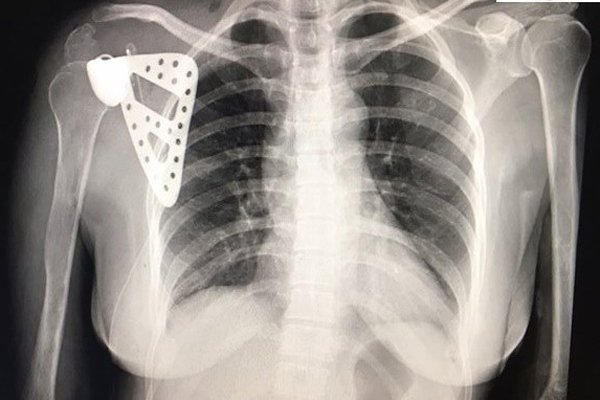

Chủ quan với cơn đau bả vai, cô giáo Hà Nội bị ung thư xương mà không biết

Sống khỏe - 06/01/2020 12:13

Chị Thúy chịu đựng cơn đau âm ỉ như kiến cắn ở bả vai suốt 5 năm. Chỉ đến khi không nâng tay được mới...